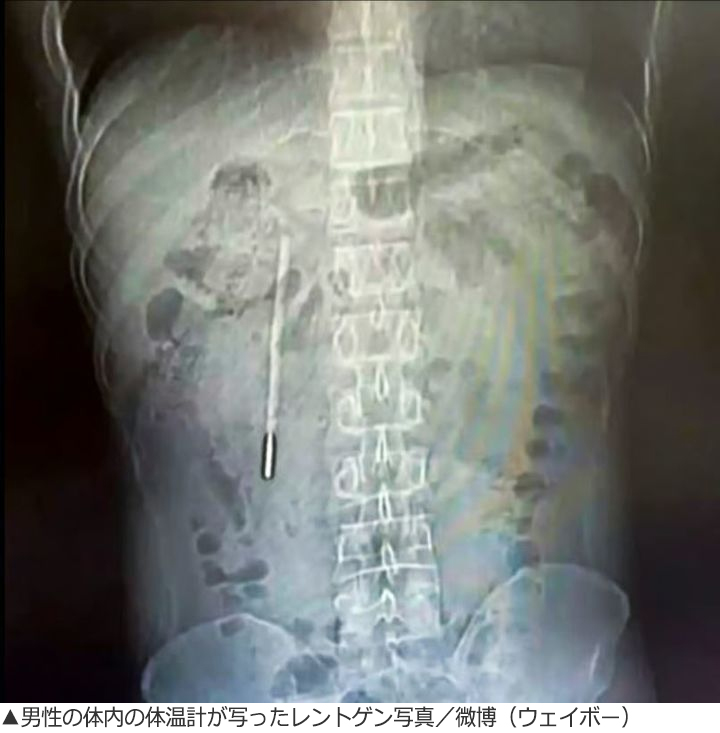

【写真】レントゲンに写った体温計

精密検査の結果、この物体は幼い時に飲み込んだ水銀体温計だったことが分かった。体温計は長期にわたり十二指腸に引っかかった状態が続いていたが、先端が腸の壁に触れているため穿孔(せんこう)や内出血を引き起こす恐れのある危険な状態だったという。

医療チームは内視鏡を使って約20分かけて体温計を取り出した。体温計は長期にわたり胆管近くにあったが、破損はなく水銀も漏れ出していなかった。ただし外の目盛りはほぼ消えてしまっていた。